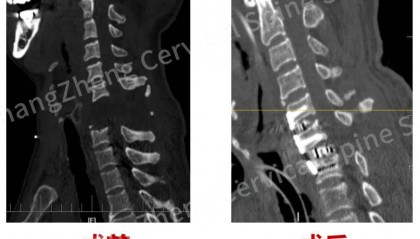

全球罕见!“身首离断”患者被救回 主刀医生:术毕两月整,已脱离呼吸机半月

8月18日,海军军医大学第二附属医院(上海长征医院)对一例“身首离断”式的罕见严重颈椎骨折脱位的患者...